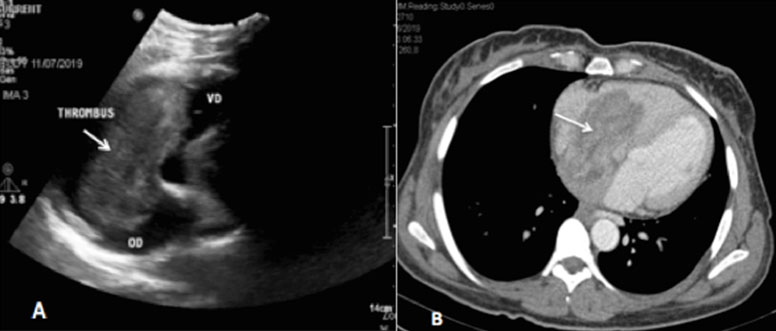

Since the timing for the acquisition of the images was not appropriate, we could not achieve uniform homogenous venous opacification. Therefore, a second look Doppler ultrasound was performed demonstrating a hypoechoic tubular paravertebral structure, between the IVC and the uterine appendices. This structure continued until the renal area where it joined the IVC, in favor of right ovarian vein thrombophlebitis. Ultrasound also identified an abnormal soft hypoechoic tissue in the IVC (Figure 3) reaching the right atrium and ventricle (Figure 4A). Anticoagulation was started immediately with enoxaparin 0.4 mL (18,000 Units) subcutaneous injection twice a day in the first week, then she was maintained on rivaroxaban 20 mg daily and the surgery was delayed. Computed tomography scan at six months showed a persistence of the tumoral OVT reaching the right atrium and ventricle (Figure 5). It also demonstrated an increase in the tumor size and the appearance of peritoneal and pericardial effusions. Rivaroxaban was maintained and chemotherapy (carboplatin-paclitaxel) was started. No follow-up study was obtained as the patient died after one month.

Figure 3: Ultrasound images showing a hypoechoic soft tissue into the IVC.

Figure 4: Ultrasound (A) and contrast-enhanced computed tomography (B) images showing the thrombosis reaching the right atrium and ventricle.